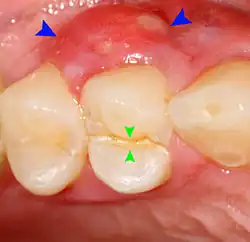

Decay (green) with apical abscess (blue) -